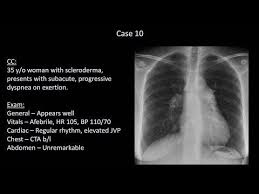

How To Interpret A Chest X Ray Lesson 10 Self Assessment Part 2 Youtube In 2020 Self Assessment X Ray Assessment